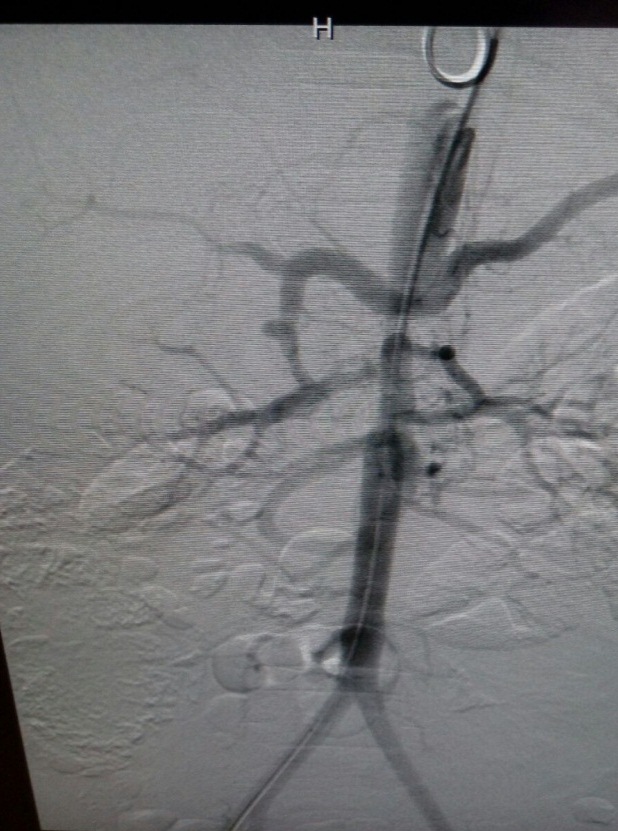

DIAGNÓSTICO FINAL: sindrome de aorta media

El síndrome de aorta media (SAM) consiste en una estenosis de la aorta abdominal generalmente con inclusión de las arterias renales y viscerales. Es un síndrome poco frecuente, aunque se considera una causa importante de hipertensión arterial (HTA) en niños y adolescentes. Se cree que su origen embriológico se debe a un fallo en la fusión de las dos aortas dorsales y la etiología es idiopática en un alto porcentaje. Su localización es interrenal en el 54% de los casos. Clínicamente cursa con HTA, sintomática o no. A la exploración puede apreciarse soplo abdominal, pulsos femorales disminuidos o ausentes y diferencia de TA entre miembros superiores e inferiores. El diagnóstico definitivo se alcanza por arteriografía y angio-RM, principalmente (2).

La aproximación terapéutica incluye el manejo médico inicial (tratamiento antihipertensivo), continuando con técnicas invasivas como angioplastia y/o intervención quirúrgica (prótesis, injertos u otras técnicas). El tratamiento médico conservador es factible hasta que el control médico de la hipertensión sea insatisfactorio, la función renal esté en riesgo o haya síntomas de claudicación de miembros o isquemia intestinal (2).